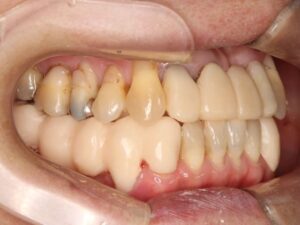

この方の場合は、上下顎の奥歯同士がかみ合っていない事、上の前歯が下の前歯を覆うかみ合わせになっていない事が問題で、受け口(反対咬合)の噛み合わせを改善する治療が必要でした。そこで、虫歯の治療も必要でしたが、それに先駆けて、上下顎の歯並びの位置を合わせる為、歯の矯正治療で歯並びを適正に合わせる治療から始めました。

半年間の保定期間の後、歯を欠損した部分などがある方の場合は、被せ物やテレスコープ義歯で治療していきます。こちらは、先ずは被せて治す必要のある部分を仮の歯で治したところの写真です。

治療前は反対咬合で前歯がかみ合っていませんでしたが、ワイヤーでの矯正治療だけで下顎は正常咬合の骨格まで後へ下がりました。反対咬合の人の場合、外科矯正になる事も多いのですが、当院で行っているMEAWのワイヤー矯正で手術が必要な外科矯正を避ける事が出来てよかったです。